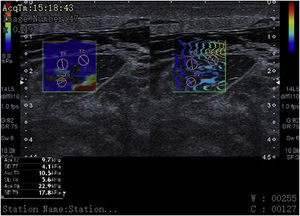

Finally, we have described and implemented highly innovative ultrasound techniques for critical patients with excellent diagnostic capabilities. However, they are still underused and further implementation is required.10 A clear example of this is the use of the “M-mode” ultrasound to analyze muscle fasciculations, color Doppler, the use of contrast-enhanced ultrasound (CEUS) to study muscle perfusion, and the visualization of microvascularization using special software (SMI) to demonstrate muscle flow unseen with color Doppler, or the use of elastography to assess muscle elasticity or rigidity in the diagnosis and follow-up of critical patients, with an area under the ROC curve of 0.972 (95%CI, 0.916–1) (Fig. 1).

Elastography: cross-sectional view of the rectus femoris muscle in a 55-year-old patient with multiple organ failure showing kilopascal values that translate into muscle stiffness in various regions of interest (ROIs) (pink circles) at the bottom of the image. The presence of interfascial and intramuscular fluid becomes evidente here too.